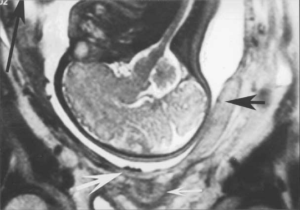

Толщина и расположение плаценты на УЗИ

Утолщение или, напротив, уменьшение толщины «детского места» является прямым следствием и показателем ее преждевременного старения. Увеличение толщины (более 4 см.) может происходит из-за резус-конфликта, инфекционного заболевания или являться следствием сахарного диабета матери.

Пространство низкой эхогенности между маткой и плацентой является признаком преждевременной ее отслойки. Дополнительными признаками отслойки являются:

- гиперэхогенность одной из долей органа, возникшая как следствие кровотечения;

- образование кровяного сгустка, прилегающего к «детскому месту».